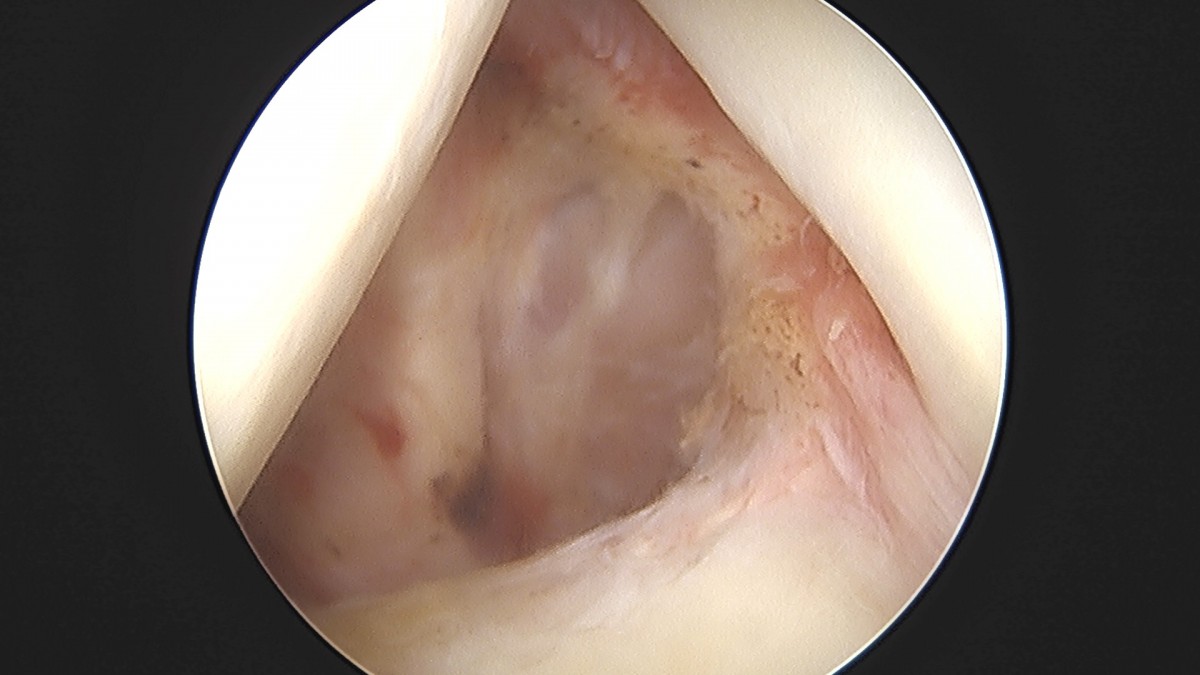

이재상원장님 어깨 견봉하 감압술 및 관절낭 이완술 양명O 환자

작성자 최고관리자 댓글 0건 조회 788회 작성일 25-09-16 15:33